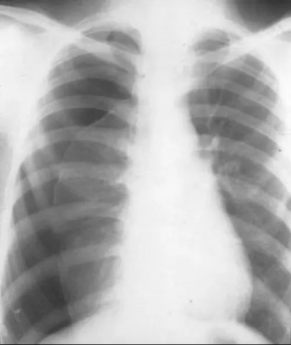

案例分享:一名17岁身材高瘦的青少年在体育课上参加跑步运动时,十几分钟后自诉感到胸闷、喘不过气来,通过120急救中心,医务人员及时赶到后进行吸氧等抢救措施并立即送往医院,经过及时处理后患者自诉症状有所缓解,经胸部CT检查后医生诊断为右肺气胸,情况非常紧急,医生紧急为他实施了胸腔闭式引流术,通过胸腔引流瓶引流出气体后,患者自诉胸闷的症状立马得到缓解,经过住院观察一段时间后,复查CT肺完全复张,恢复良好已出院。